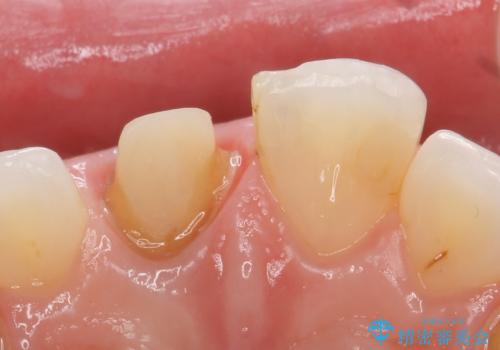

- 右上1の前歯の見た目が気になるので被せ物をやり替えたいといらっしゃった方の症例です。

再根管治療終了後、オールセラミッククラウン(スペシャル)によって隣在歯に合わせた補綴を行いました。

- オールセラミッククラウン(スペシャル)…¥130,000、仮歯…¥10,000、ファイバーコア…¥20,000費用は治療当時の料金となります